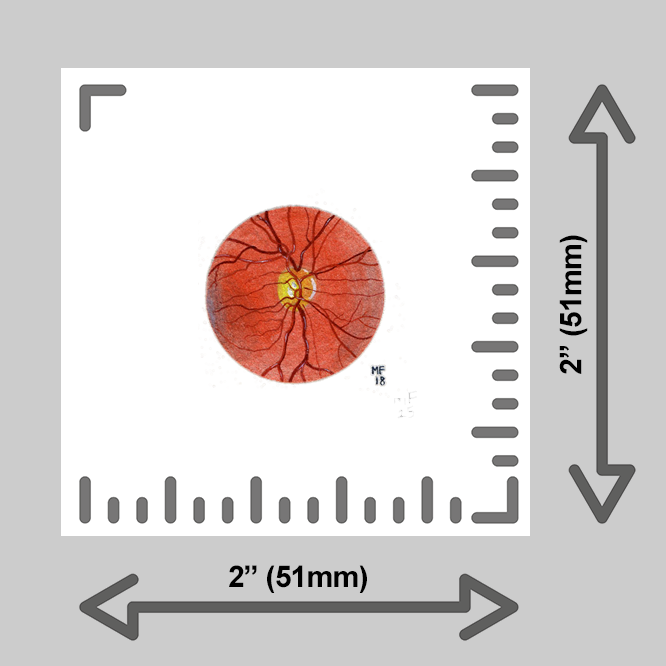

learn more about these prints below:

Each tiny print is made by hand by yours truly in my Michigan studio using an EPSON P600 printer. Only the finest heavy matte archival, museum-quality, paper is used; color and finish are inspected thoroughly for each print before framing and shipping.

Want to upgrade your print? Add a wee frame! You have four options for framing your tiny print:

A sturdy 2×2” wood frame with a saw tooth hanger, or,

A 2×2” clear acrylic magnet frame, or,